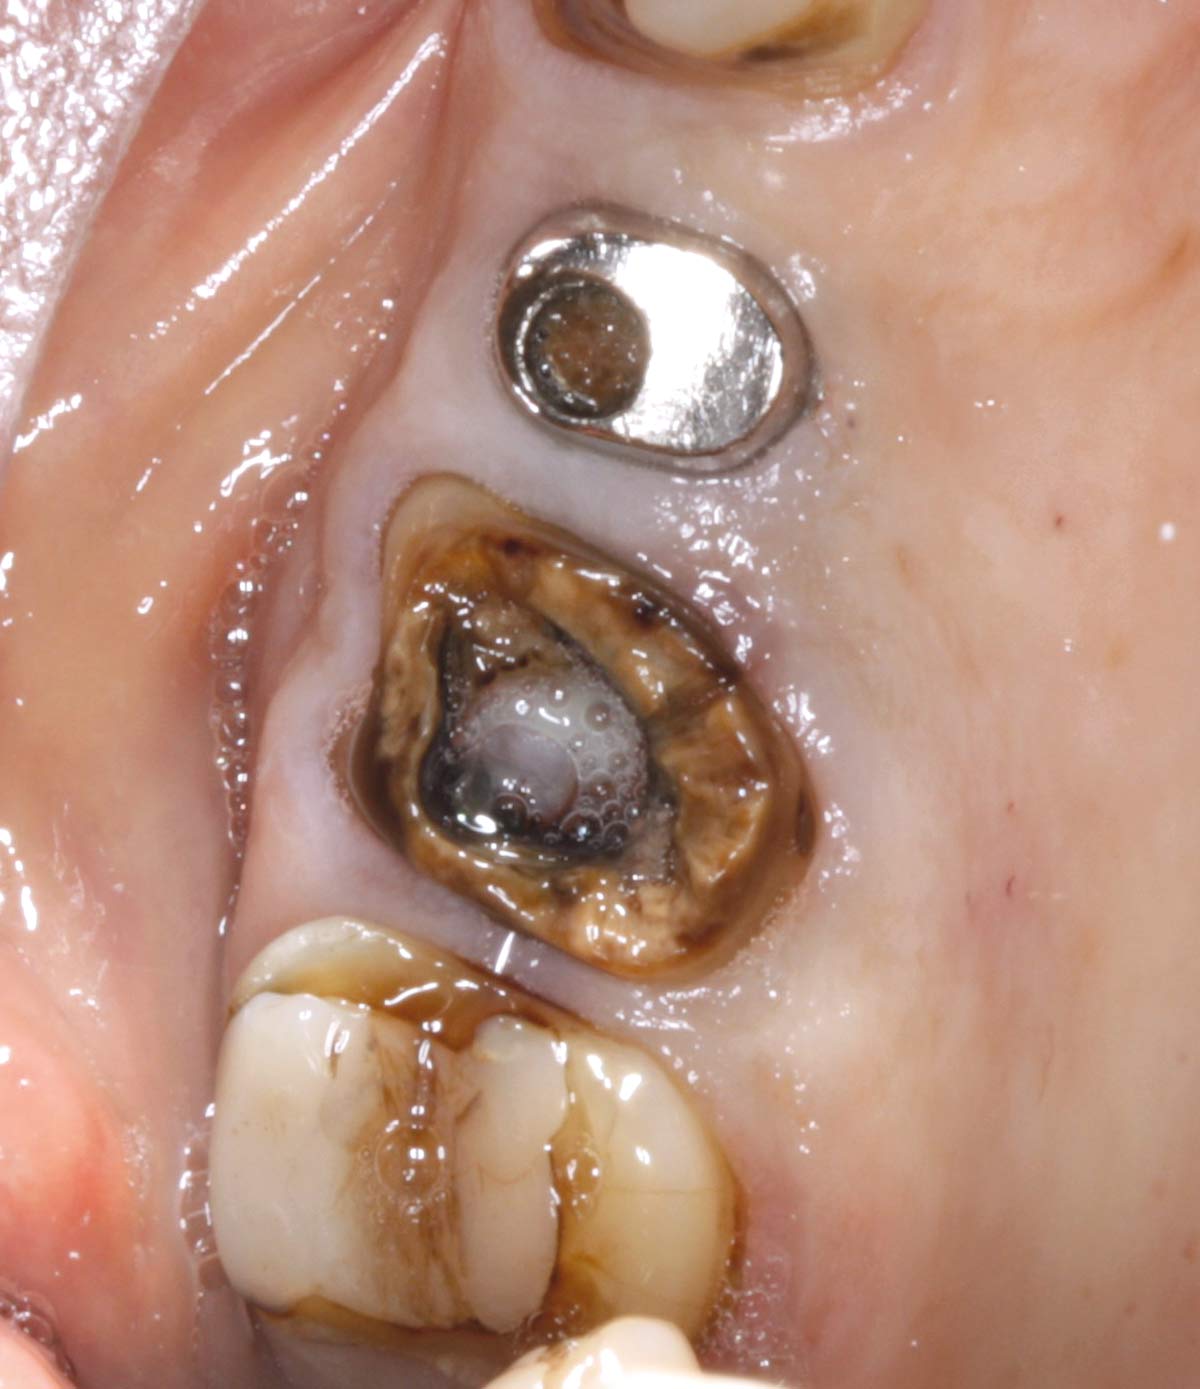

02/07 - Situation after tooth extraction.Socket preservation with permamem® - Dr. M. Turco

Situation after tooth extraction.